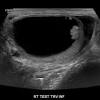

Signs And Symptoms Of Testicular Cancer Ultrasound Dimensions Dublin from ultrasound.ie What are the symptoms of testicular cancer? A dull ache in the lower abdomen or the groin. What's more, there's no shame in talking about it. Lumps can be as small as a pea. Testicular cancer is cancer that starts in the testicles. Depending on the type and stage of testicular cancer, you may receive one of. Q breast growth or soreness: Doctors treating testicular cancer will aim to limit treatment side effects.